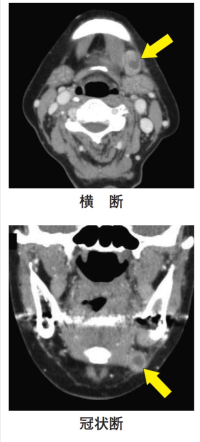

78歳の女性。抜歯後の治癒不全を主訴として来院した。左側の下顎臼歯部歯肉に硬結を伴う潰瘍を認め、左側顎下部に無痛性の腫脹を認める。初診時のエックス線写真、造影CT横断像と冠状断像及び下顎歯肉部の生検時のH-E染色病理組織像を別に示す。

矢印で示すのはどれか。1つ選べ。

d. 転移リンパ節